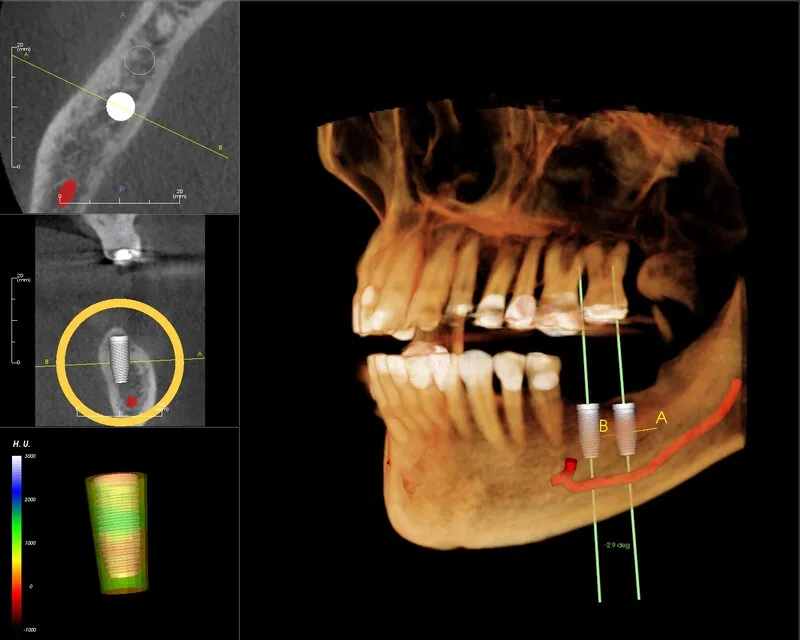

Chụp CT Conebeam là một công nghệ chụp cắt lớp vi tính sử dụng tia X, giúp tạo ra hình ảnh 3D chi tiết của các cấu

Chụp CT Conebeam là một công nghệ hiện đại, đặc biệt được ứng dụng rộng rãi trong các lĩnh vực nha khoa như chỉnh nha, cấy ghép

Chụp X-quang răng là bước quan trọng trong việc chẩn đoán và điều trị các vấn đề về răng miệng, giúp bác sĩ xác định chính xác